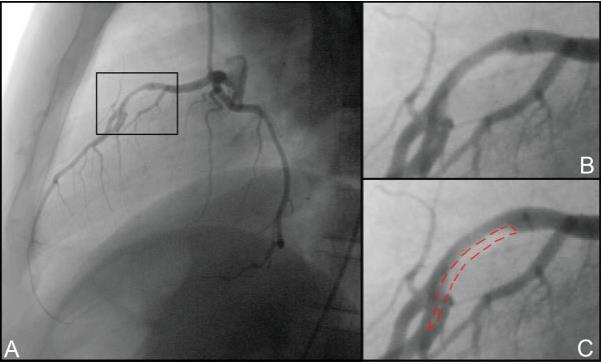

冠状动脉造影是临床诊断冠状动脉病变的重要影像学检查方法,能够清晰显示冠状动脉的血流情况及血管的狭窄程度,被广泛认为是诊断冠心病的“金标准”。冠脉造影通过注入造影剂后获取血管影像,医生依据影像对冠状动脉的病变情况进行诊断与介入手术治疗。

本项目提出一种基于视觉 Mamba 神经网络的冠脉造影狭窄智能检测技术,并设计了两个创新性的网络架构:Mamba-CAGSeg和 Mamba-CAGDetect,分别用于血管精确分割和狭窄检测,旨在提升图像分析的自动化和准确性,从而解决传统手工分析存在的低效和主观误差问题。该技术在检测精度和定位效果方面表现出色,成功应对了冠脉图像复杂场景中的狭窄检测难题,同时具备高效的实时推理性能。